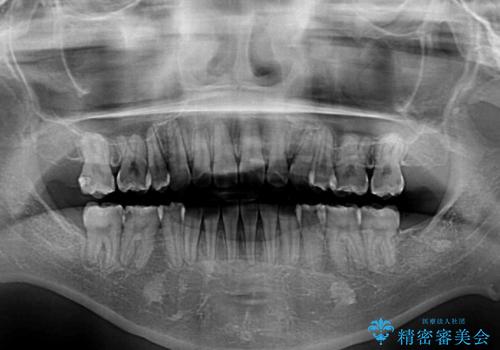

上下の八重歯とクロスバイト ワイヤー装置での抜歯矯正

- 八重歯とクロスバイトを気にして来院された患者様です。

上下ともに八重歯が顕著であり、前歯のクロスバイトがあったため、上下左右の第一小臼歯4本を抜歯し、ワイヤー装置での抜歯矯正を行うこととしました。